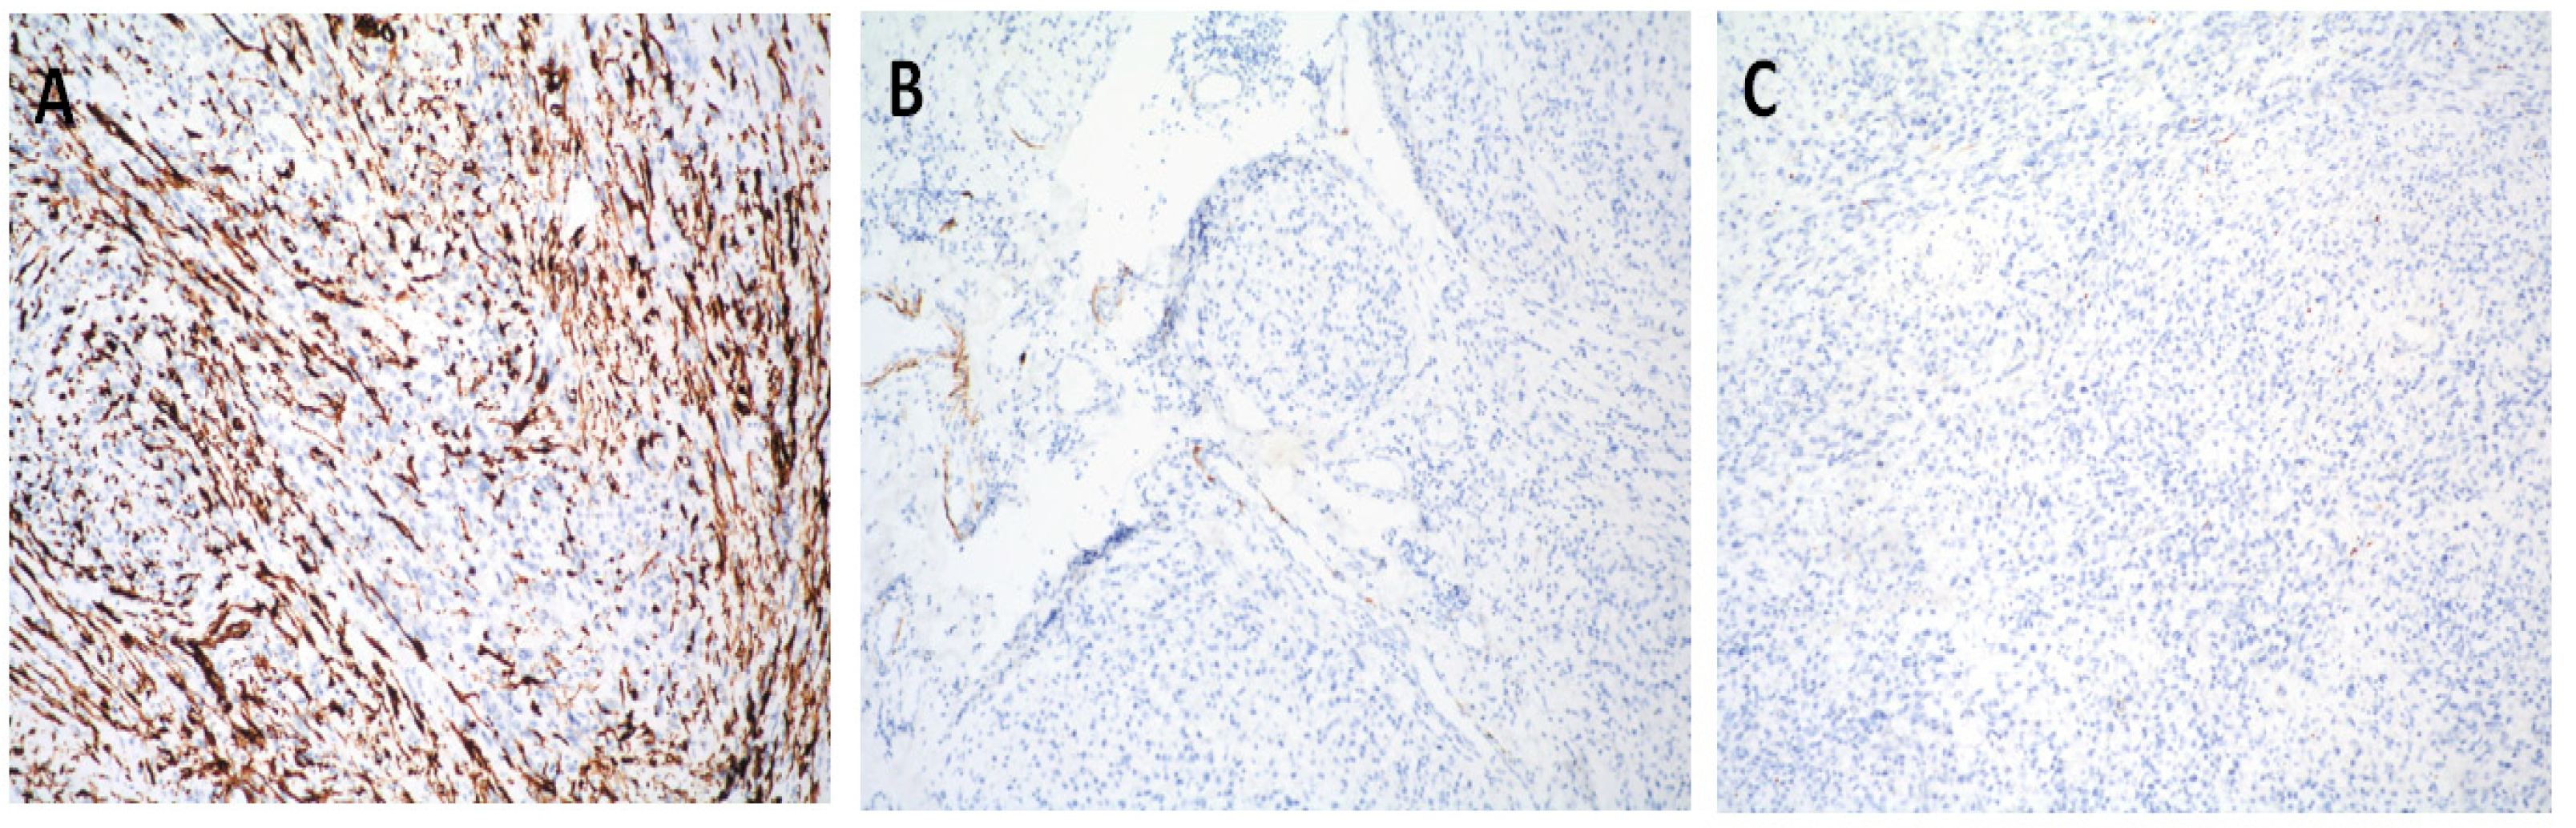

2. Case Report